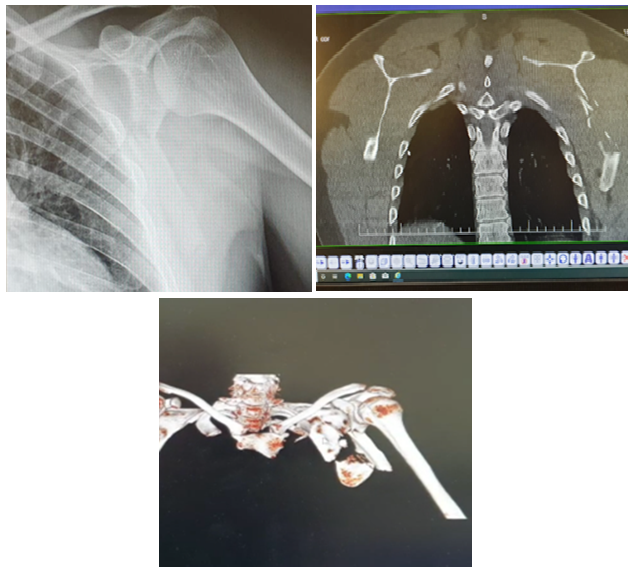

Congenital Pseudoarthrosis of Clavicle: A Case Report and Review of Literature

Abdulaziz Saleh Alharthi, Mokhtar Ahmed Alsayed

International Journal of Innovative Research in Medical Science·August 16, 2022